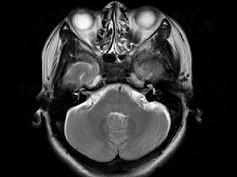

女,41岁,阵发性头痛伴恶心、呕吐20余天,CT影像如图,最可能的诊断为 ( )

• A.双侧筛窦息肉

• B.双侧筛窦息真菌感染

• C.双侧筛窦过敏性炎症

• D.双侧筛窦炎

• E.双侧筛窦未见明显异常

答案: D